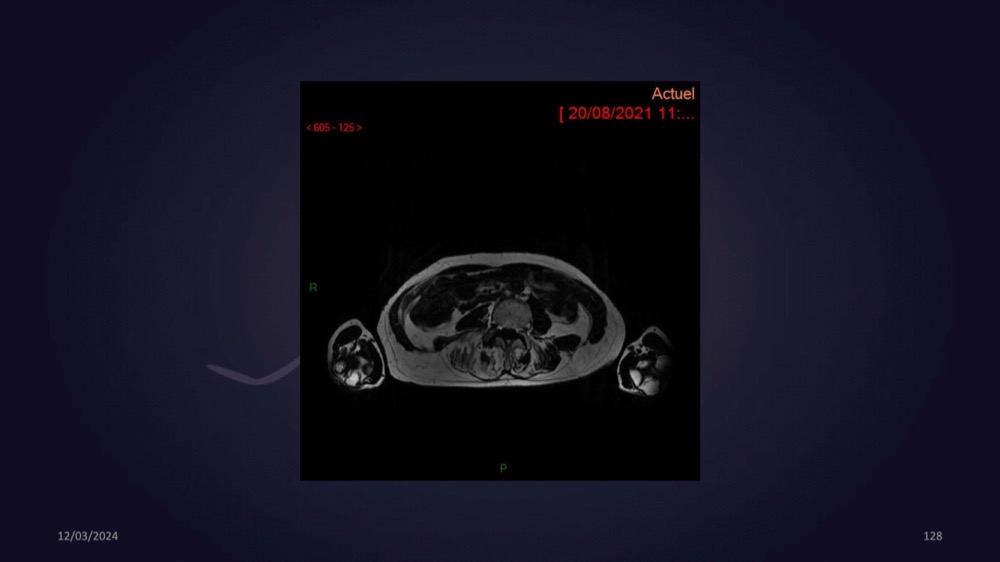

Mezhgani / Dimitri Boulos / Carlier 23/03/2022